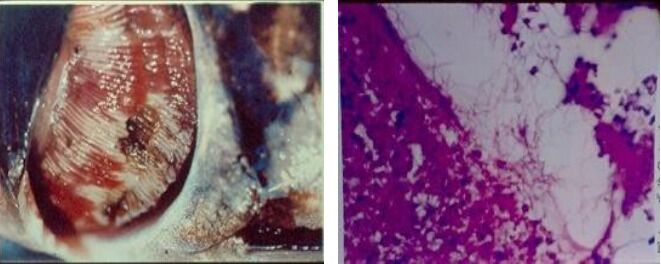

- Lesion:爛鰓、 可見菌塊

體表潰瘍,但內臟完好! |

二級鰓薄板爛掉 |

脊椎骨肌肉裸露 |

- Flavobacterium columnare: columaris disease(淡水魚)

- 夏天好發,爛鰓較嚴重,進展快,全面性壞死、浮頭

- 二級鰓薄板增生、融合